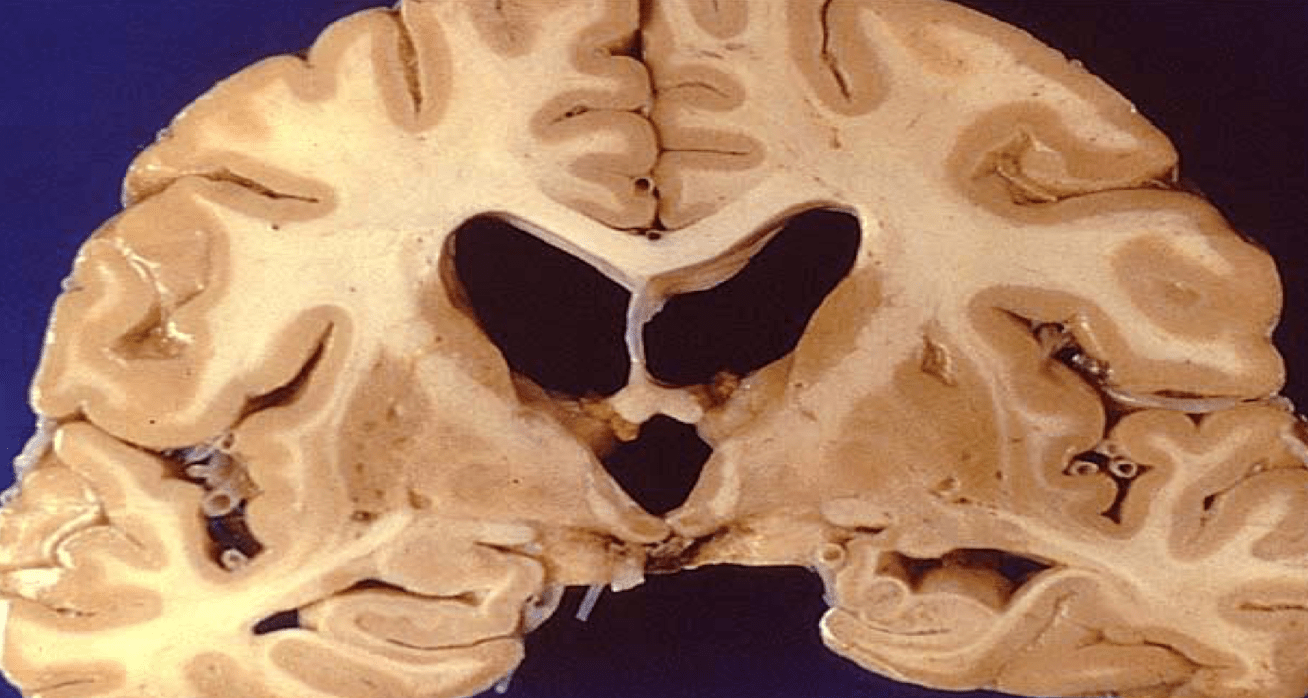

this enlargement of both the lateral and third ventricle suggests what pathology

hydrocephalus of some sort

**in this case specifically normal pressure hydrocephalus